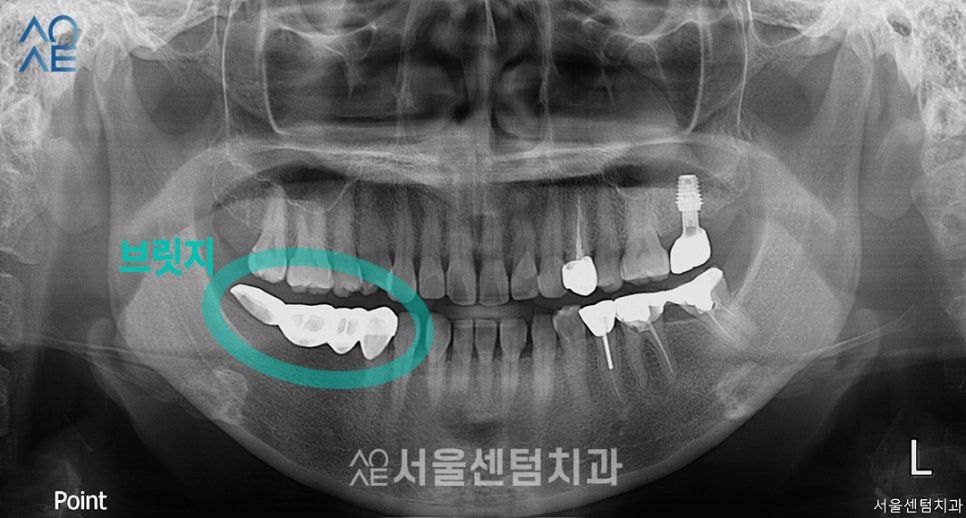

위 엑스레이 사진 상으로는 왼쪽

실제로는 오른쪽 아래쪽을 봐주시면

브릿지라는 치과 보철물이 있죠?

기존 어금니를 이미 상실한 상태여서

보철물을 통해 치아의 기능만 회복한 상태였습니다.

또 전체적으로 잇몸이 좋지 않아

조금 내려가 있는 상태였고요.

| (1) 현재 상태🔹 전체적으로 잇몸 내려감🔹 왼쪽 아래 브릿지 있음🔹왼쪽 아래 어금니 상태 좋지 않음 |

| (2) 치료 계획🔹왼쪽 아래 어금니 발치 후 임플란트 식립🔹뼈이식 동반 필요🔹2차 수술까지 진행 예정 |